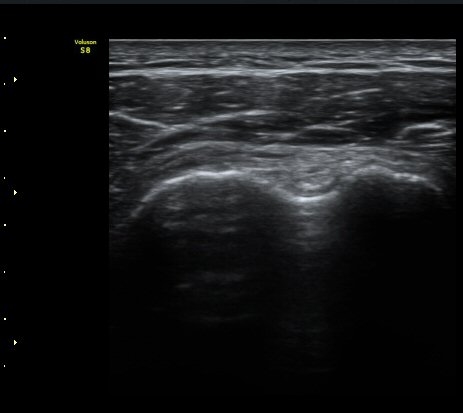

ÀÌµÎ¹Ú±Ù°Ç È¾´Ü¸é°Ë»ç¿¡¼­ ƯÀÌ ¼Ò°ßÀ» º¸ÀÌÁö ¾ÊÀ½(»çÁø 1, 2).

±Ø»ó°Ç Á¾´Ü¸é°Ë»ç¿¡¼­ ´ë°áÀý°ú »ó¿Ï°ñµÎ ÀÌÇàºÎÀ§¿¡ ÇÇÁú°ñ ¿¬¼Ó¼º ¼Ò½ÇÀ» º¸ÀÓ(±×¸² 3, 4, 5)